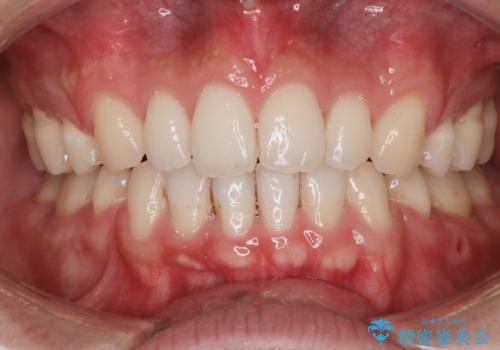

前歯の隙間を閉じたい 口元も下げたい ハーフリンガルによる抜歯矯正